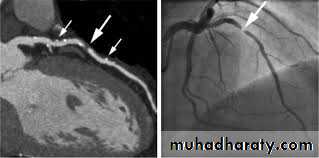

Coronary arteriography:

This provides detailed anatomical information about the extent and nature of coronary artery disease. The procedure is performed under local anaesthesia and requires specialized radiological equipment, cardiac monitoring and an experienced operating team.Management:

Percutaneous coronary intervention:

Percutaneous coronary intervention (PCI) is performed by passing a fine guidewire across a coronary stenosis under radiographic control and using it to position a balloon, which is then inflated to dilate the stenosis with or without stent implantation. PCI is mainly indicated in patient with persistent angina despite optimum medical therapy.